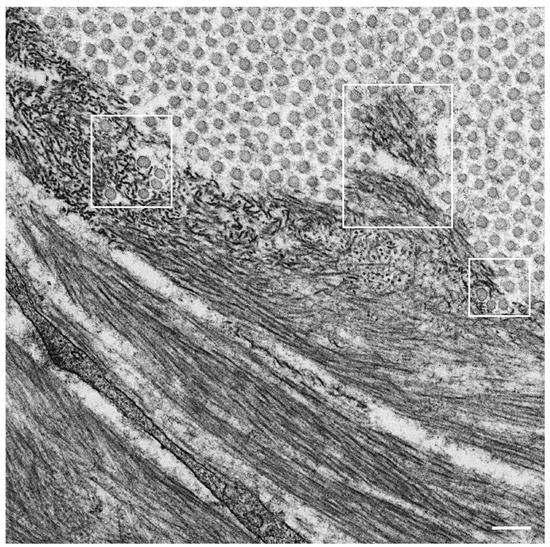

- Koike, H.; Nishi, R.; Ikeda, S.; Kawagashira, Y.; Iijima, M.; Sakurai, T.; Shimohata, T.; Katsuno, M.; Sobue, G. The morphology of amyloid fibrils and their impact on tissue damage in hereditary transthyretin amyloidosis: An ultrastructural study. J. Neurol. Sci. 2018, 394, 99–106. [Google Scholar] [CrossRef] [PubMed]